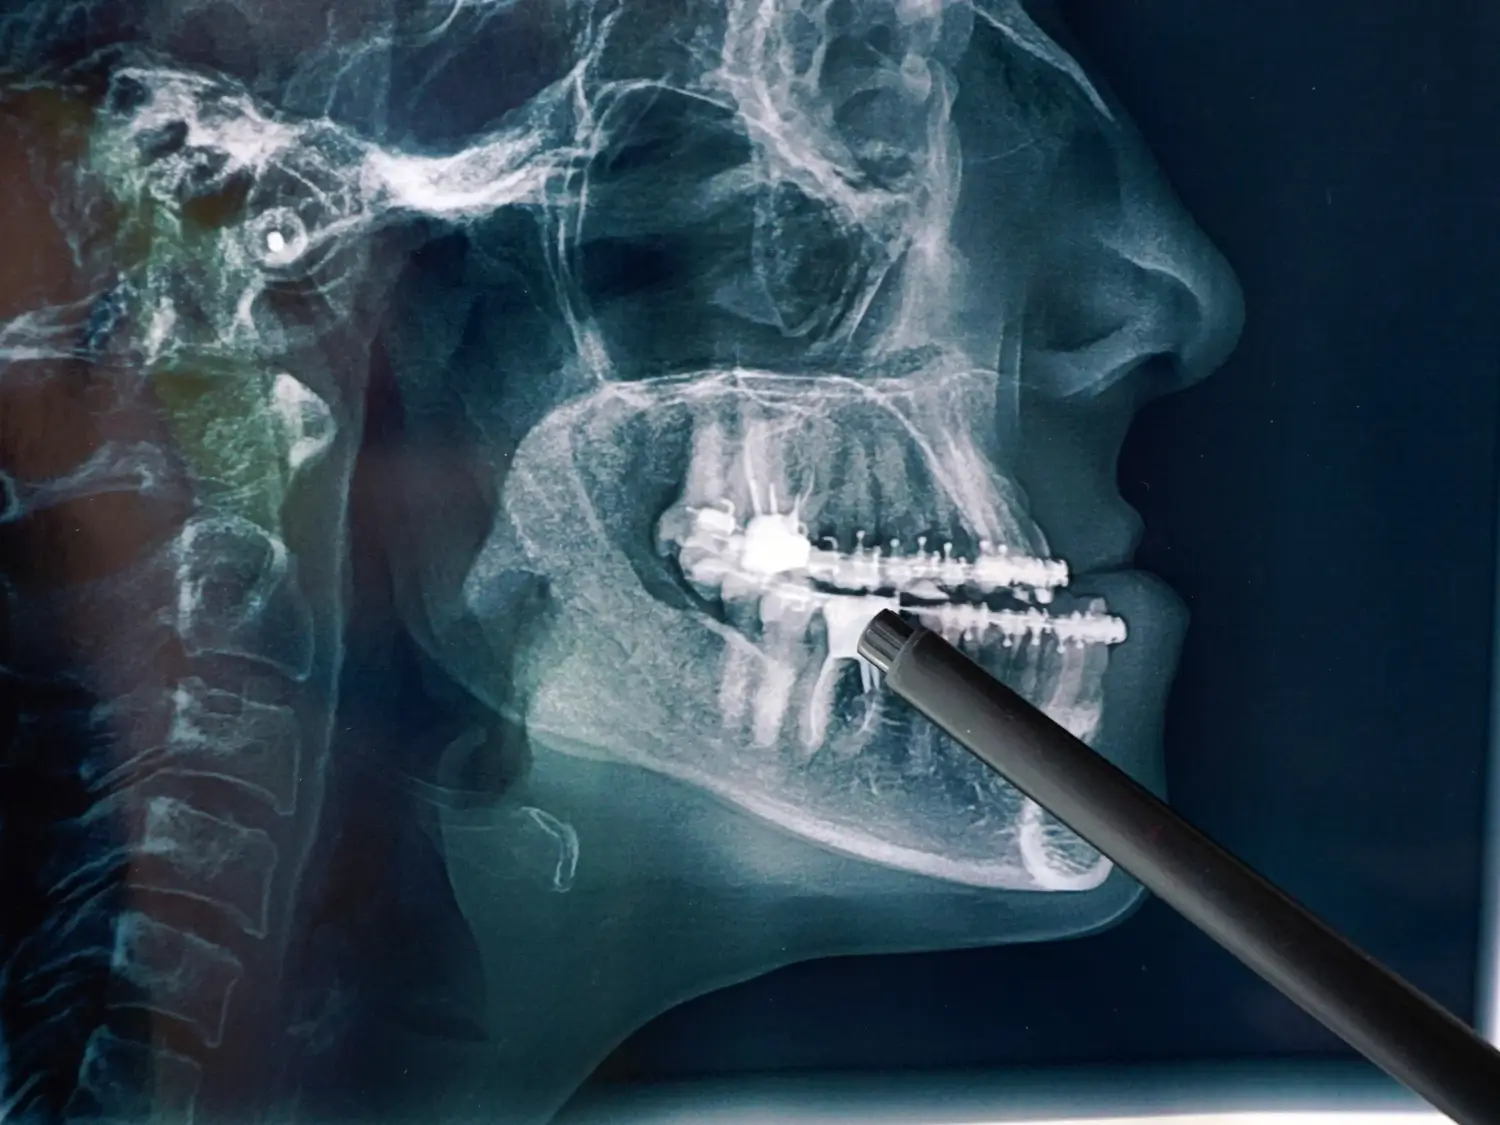

كسور وإصابات الوجه والفكين

علاج الكسور الناتجة عن الحوادث أو الإصابات، بما يشمل عظام الفك، والخد، ومحجر العين، وأيضًا تركيب شرائح ومسامير الوجه والفكين.

جراحة الكسور والإصابات

خبرتنا في جراحات الكسور والإصابات تضمن علاجاً متقدماً للحوادث والرضوض، مع إعادة بناء الفكين واستعادة الوظيفة ببكفاءة عالية